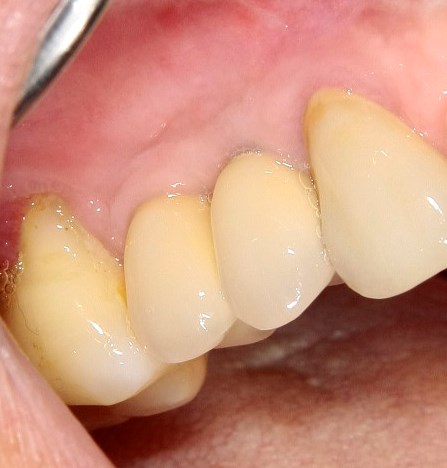

Опыт применения коллагеновой матрицы Mucograft в клинической практике.